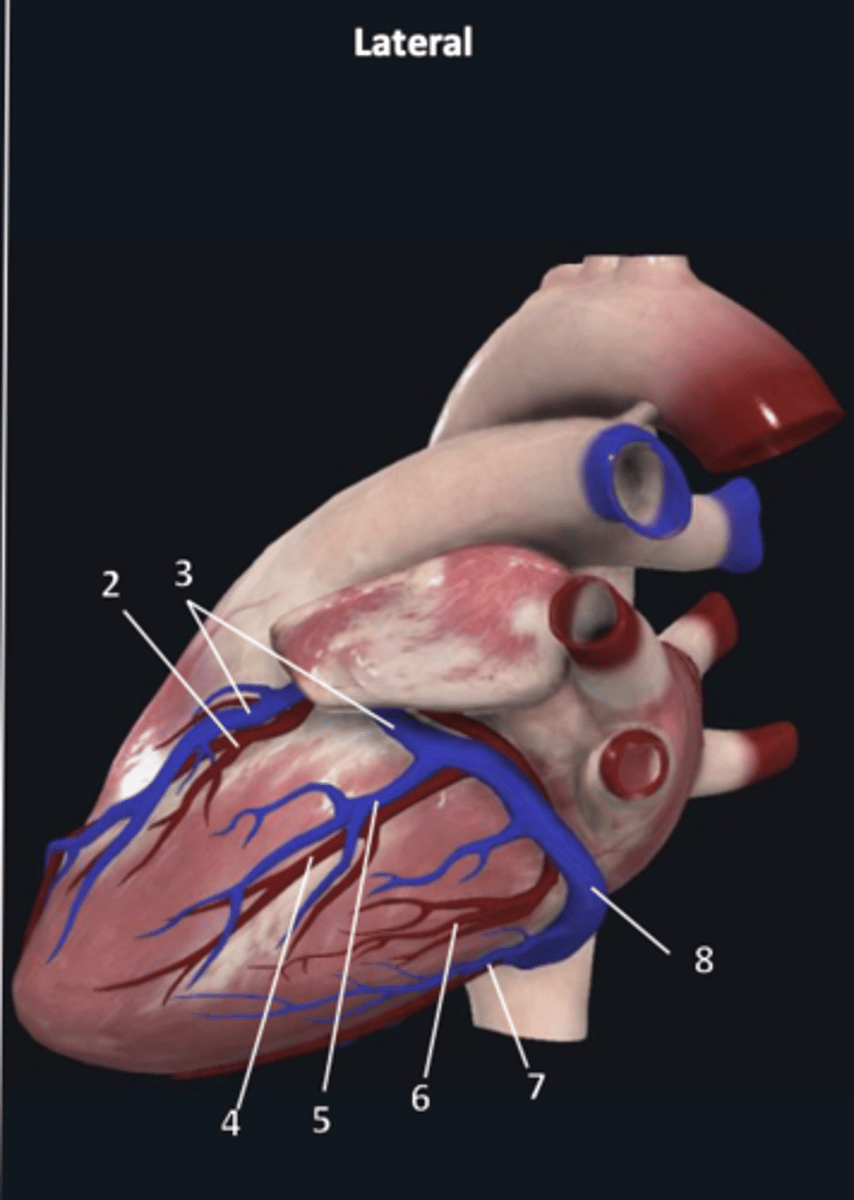

right coronary artery

1

anterior interventricular artery

2 (red)

great cardiac vein

3 (blue)

anterior interventricular artery

2 (red)

great cardiac vein

3 (blue)

left marginal artery

4

left marginal vein

5

posterior left ventricular artery

6

posterior vein of left ventricle

7

coronary sinus

8